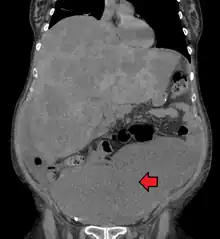

Medical imaging

A colorectal cancer is sometimes initially discovered on CT scan.

Presence of metastases is determined by a CT scan of the chest, abdomen and pelvis.[23] Other potential imaging tests such as PET and MRI may be used in certain cases.[23] The latter is often used for rectal lesions to determine its local stage and to facilitate preoperative planning.